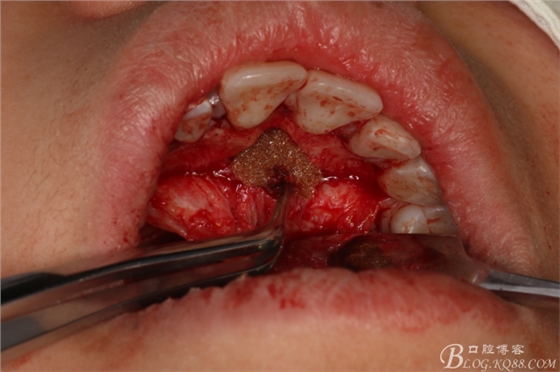

圖17.拔牙創(chuàng)口放置膠質(zhì)銀兩枚

圖18.縫合